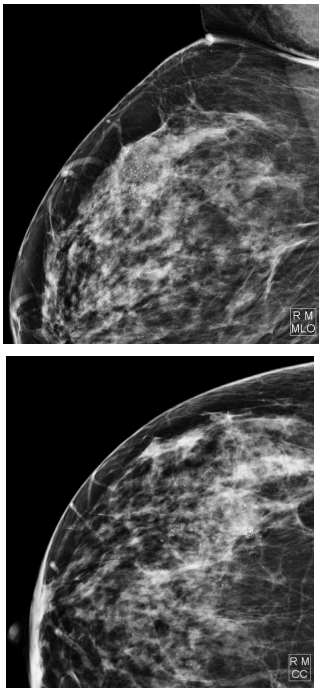

Mastologia

RMC, 58 anos, assintomática, comparece a unidade com resultado de mamografia de screening realizada há cerca de 3 meses. Relata que exames não possuem laudos pois os perdeu em uma enchente. Considerando as imagens, assinale a conduta mais adequada:

A

Encaminhar a paciente para realização de mastectomia radical.

B

Solicitar nova mamografia em 6 meses.

C

Tranquilizar a paciente, orientar benignidade do quadro e manter seguimento habitual.

D

Solicitar core biopsy, anatomopatológico e considerar imuno-histoquímica.